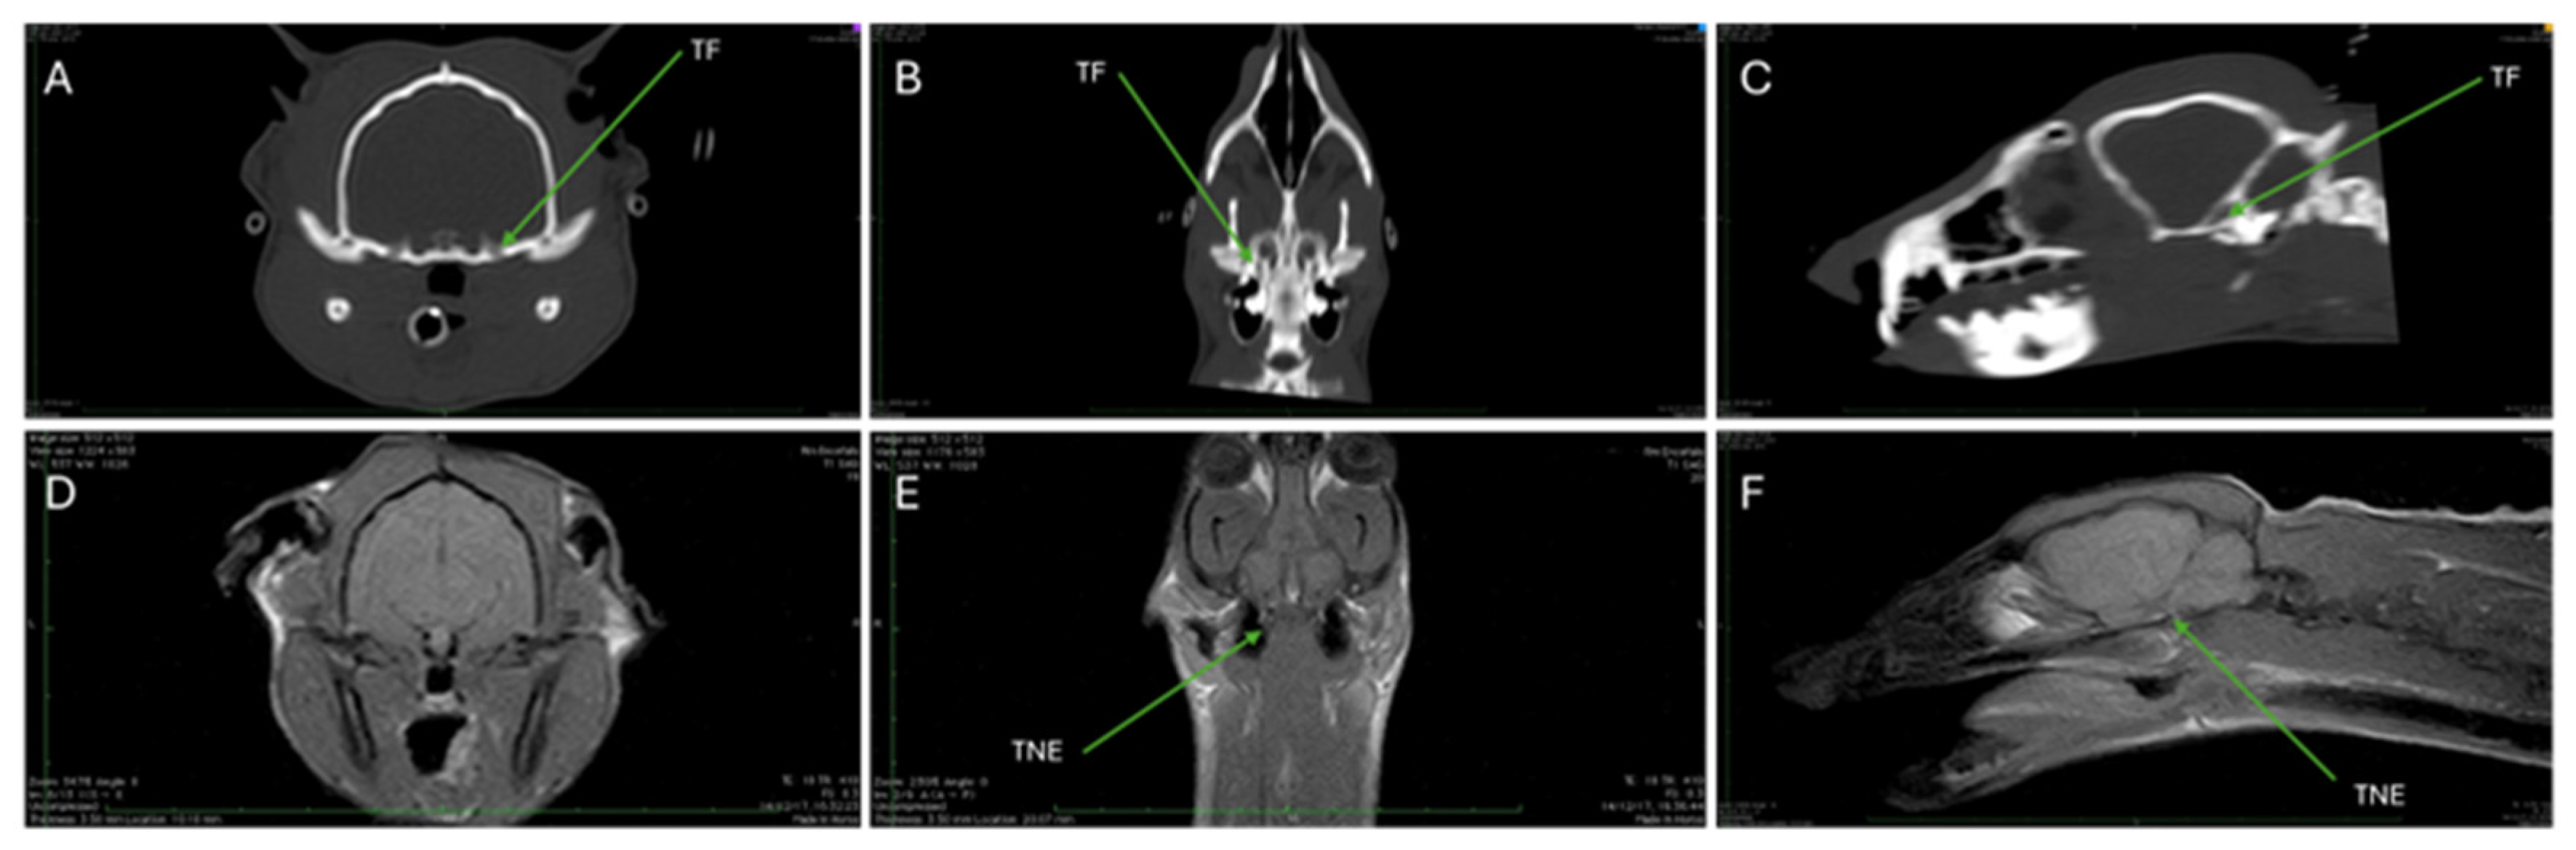

| TF | Trigeminal foramen |

| TNE | Trigeminal nerve emergency |

3.3. Magnetic Resonance Imaging (MRI)